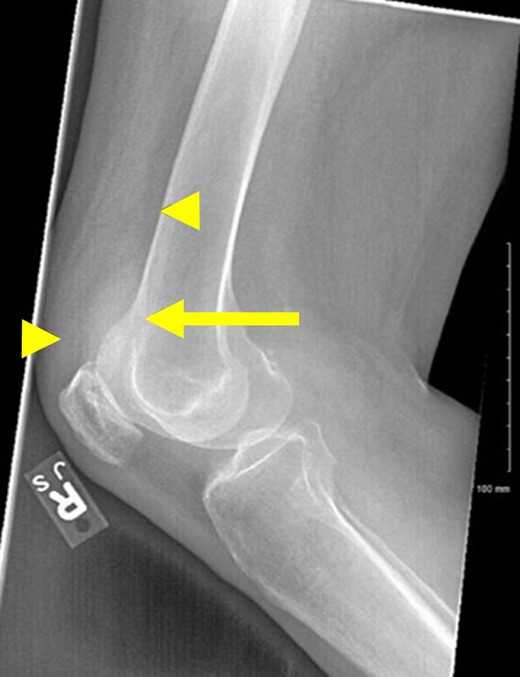

The patient’s leukocytosis improved to 14.8 K/μL but did not completely normalize prior to her undergoing an open distal pancreatectomy and splenectomy (Figs 2 and 3). The surgery was uncomplicated, and her initial recovery was as expected. On postoperative day two, she began complaining of bilateral knee pain, right worse than left. She was mildly tachycardic with a rising leukocytosis to 35.8 K/μL which had previously downtrended postoperatively (Fig. 2). Her right knee was warm, swollen, and had restricted extension. Radiographs demonstrated an effusion (Fig. 4). An urgent consult to orthopedic surgery was called. Arthrocentesis was performed which revealed grossly turbid synovial fluid with 86 350 WBCs/mm3 consistent with septic arthritis (Table 1).

Right lateral knee radiograph. The joint effusion (arrow) can be most clearly visualized between normal anterior anatomic fat pads, the quadriceps and prefemoral (arrowheads).